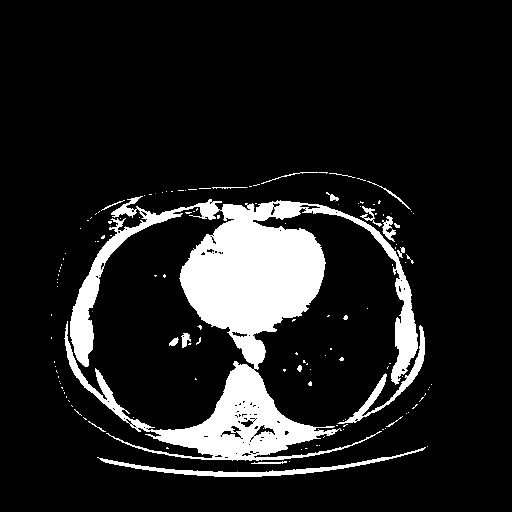

Original VENOUS CT scan

Full window (WL 1023.5, WW 4095 β†’ Low βˆ’1024, High +3071)

Actual HU range: [-1024.0, 3071.0]